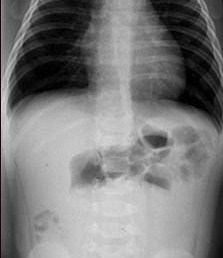

299) A 10 month old male infant is brought by his concerned mother to the Emergency room with complaints of vomiting and bloody diarrhea. Mother reports that he suffered from “stomach flu” symptoms about 1 week ago which resolved spontaneously. He had 4 episodes of vomiting since yesterday and has been crying intermittently every 15 minutes. There is no blood or bile in the vomitus. He had four loose stools with blood in it. There is no history of fever or cough or cold. His past medical history is unremarkable. On examination, temperature is 98.4F, pulse 112, respiratory rate 30/min and blood pressure at 80/50 mm hg. Oral mucosa appear moist and skin turgor is adequate. Abdomen is soft with no palpable masses. Bowel sounds are present. Stool guaiac is strongly positive. Stool is sent for cultures and abdominal x-rays are obtained. An x-ray image is shown below:

Which of the following is the most appropriate next step in managing this condition?

B) Gastrograffin enema